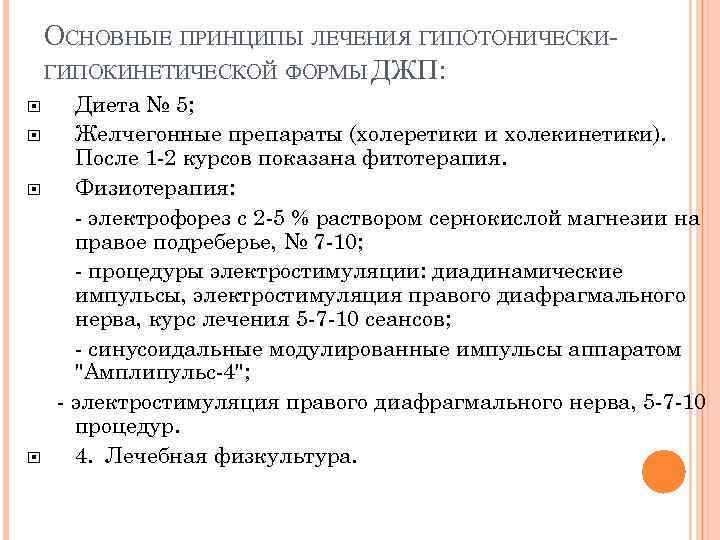

ОСНОВНЫЕ ПРИНЦИПЫ ЛЕЧЕНИЯ ГИПОТОНИЧЕСКИГИПОКИНЕТИЧЕСКОЙ ФОРМЫ ДЖП: Диета № 5; Желчегонные препараты (холеретики и холекинетики). После 1 -2 курсов показана фитотерапия. Физиотерапия: - электрофорез с 2 -5 % раствором сернокислой магнезии на правое подреберье, № 7 -10; - процедуры электростимуляции: диадинамические импульсы, электростимуляция правого диафрагмального нерва, курс лечения 5 -7 -10 сеансов; - синусоидальные модулированные импульсы аппаратом "Амплипульс-4"; - электростимуляция правого диафрагмального нерва, 5 -7 -10 процедур. 4. Лечебная физкультура.